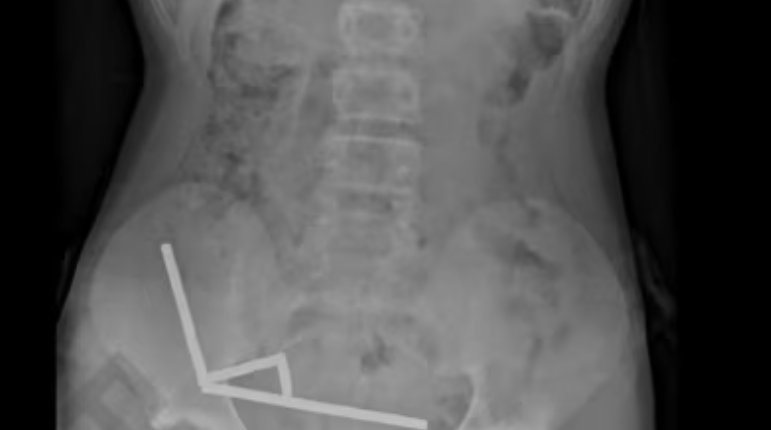

Trinaestogodišnjem dječaku na Novom Zelandu uklonjeni su nekrotični dijelovi crijeva nakon što je progutao skoro 100 magneta kupljenih preko interneta, objavio je danas medicinski časopis New Zealand Medical Journal (NZMJ). Dječak je magnete kupio na sajtu Temu.

Nakon četiri dana bolova u stomaku, tinejdžer je prebačen u bolnicu Tauranga na Sjevernom ostrvu. "Priznao je da je sedmicu dana ranije progutao između 80 i 100 snažnih neodimijumskih magneta, veličine približno 5x2 mm", navodi se u izvještaju ljekara.

Ova vrsta magneta, zabranjena na Novom Zelandu od januara 2013. Ljekari su rekli da je pritisak koji su vršili magneti izazvao nekrozu u dijelovima tankog i debelog crijeva dječaka.

Podvrgnut je operaciji uklanjanja magneta i nekrotičnog tkiva i otpušten je kući nakon osam dana u bolnici.